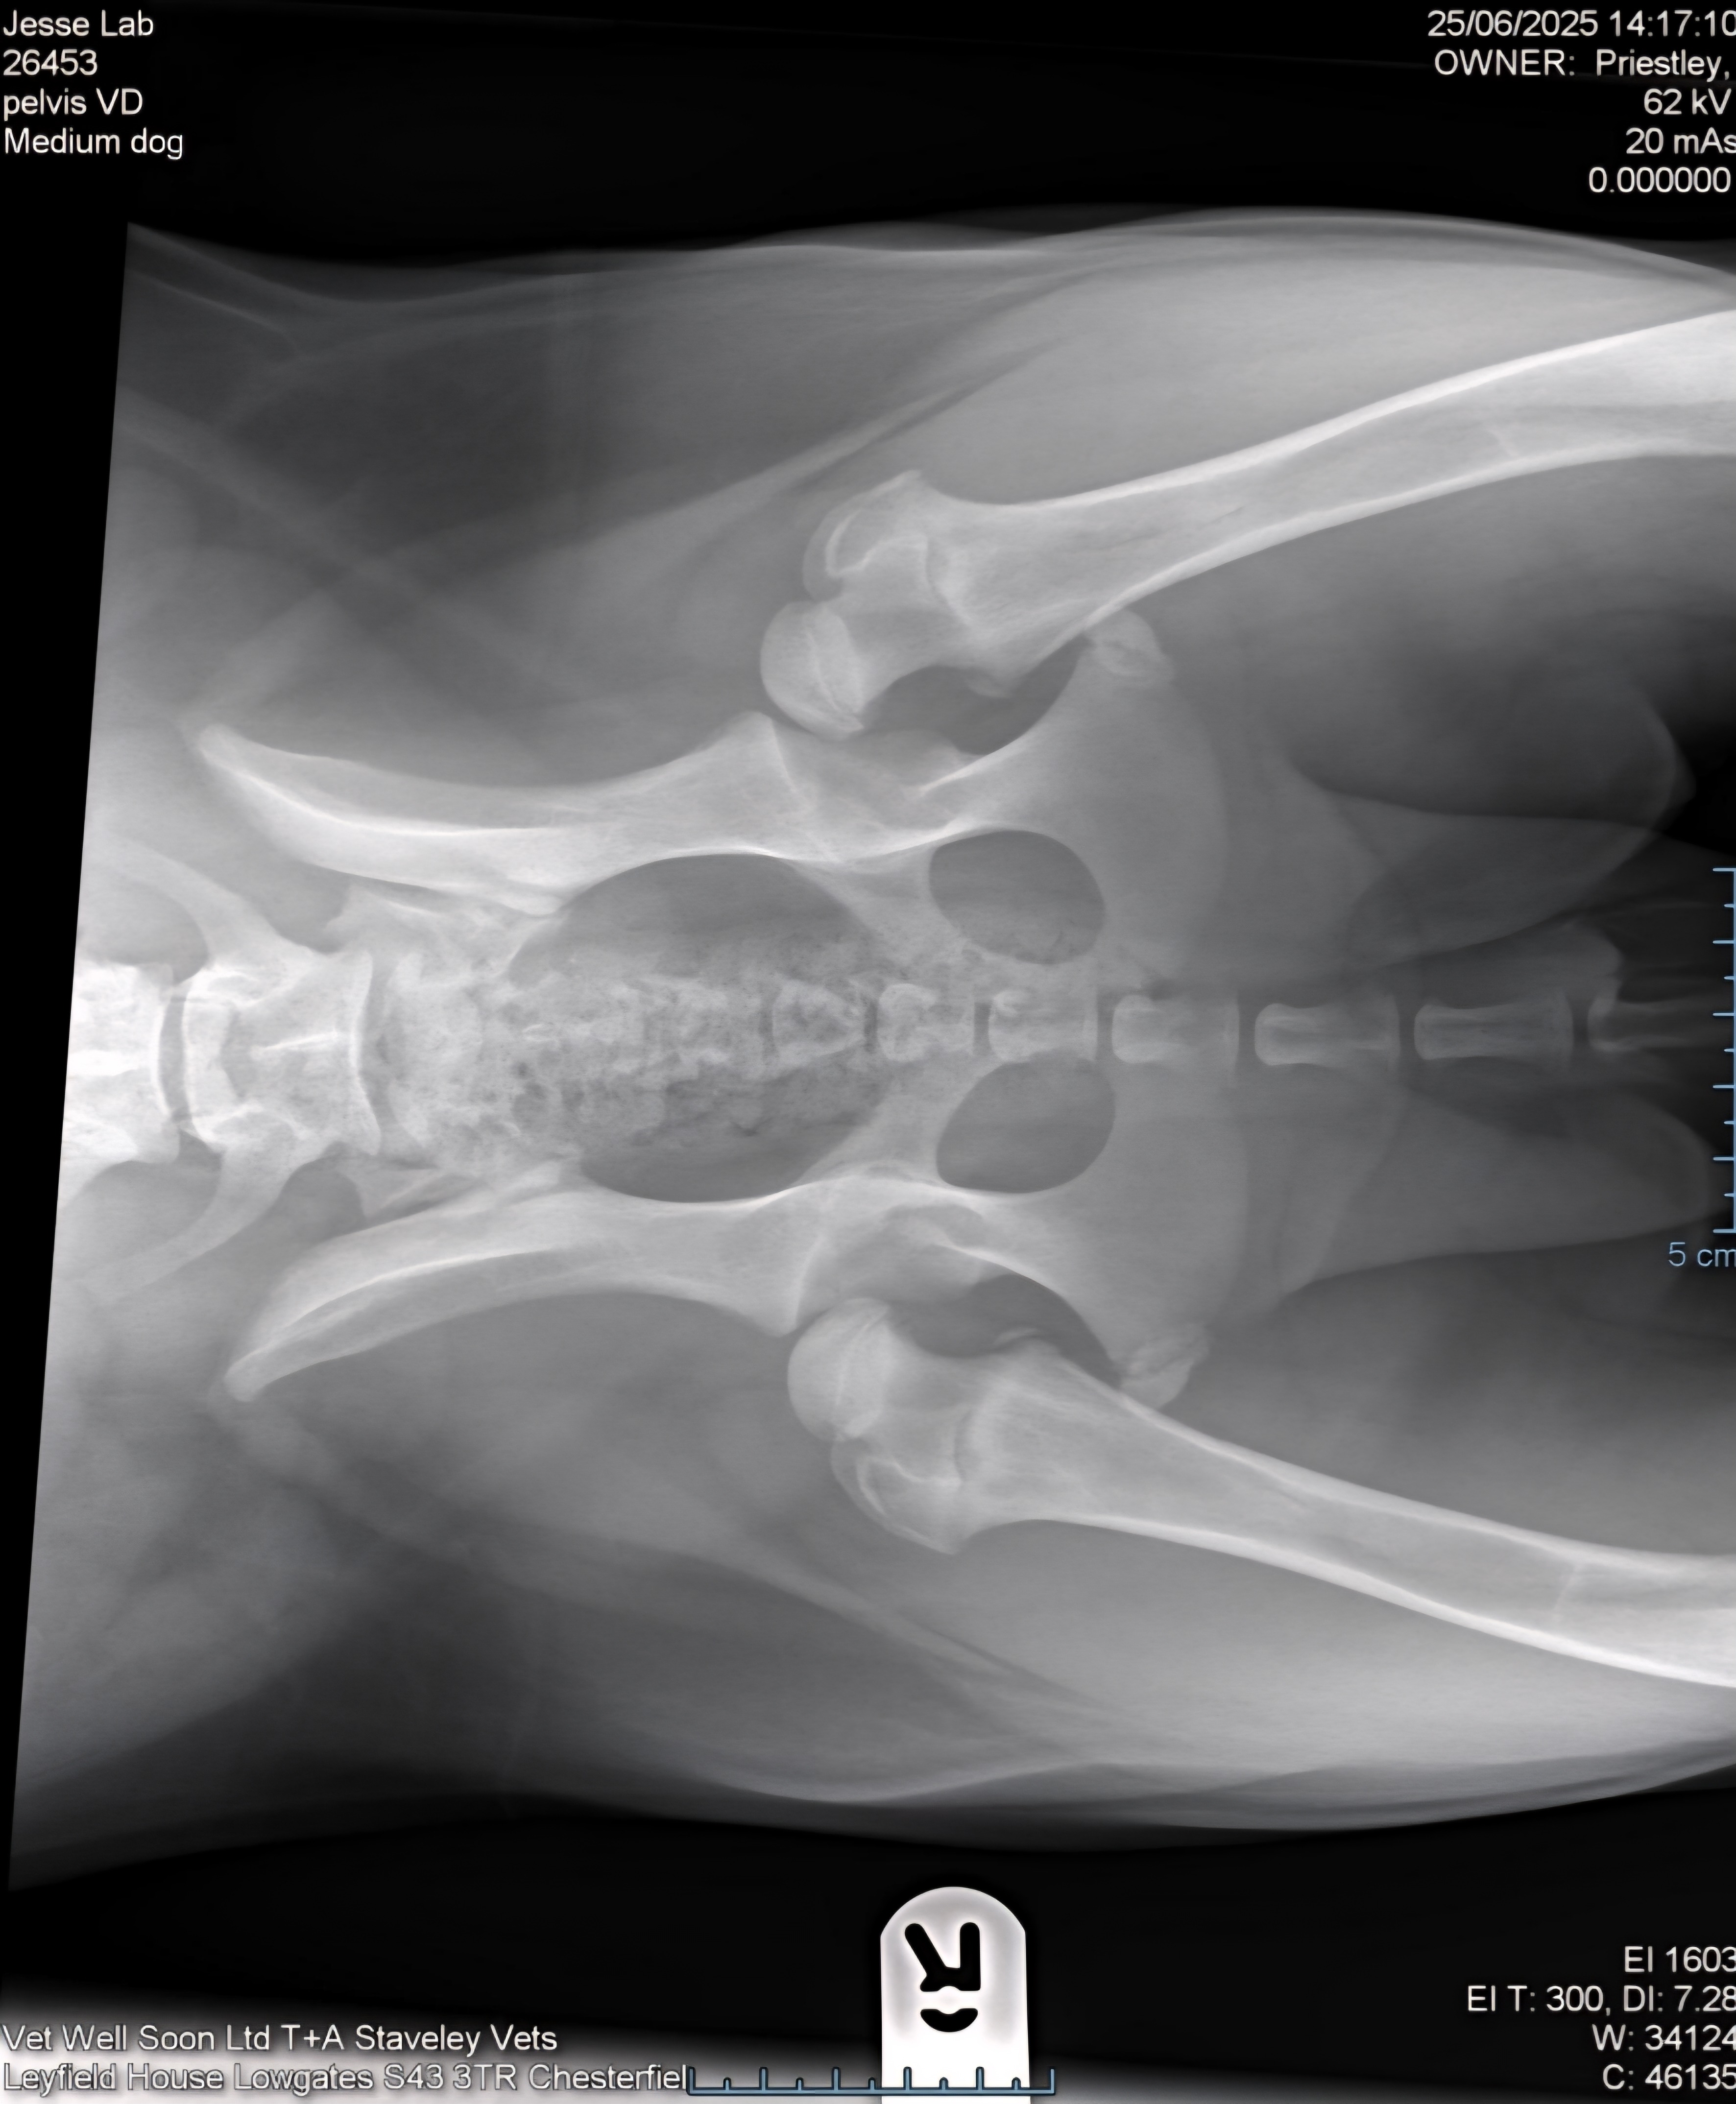

After numerous vet visits, we learned the heartbreaking truth: Jesse has severe hip dysplasia, and the only solution to give her back a happy, active life is a hip replacement surgery. The surgery is quoted at £10,000, a cost far beyond what we can manage on our own.